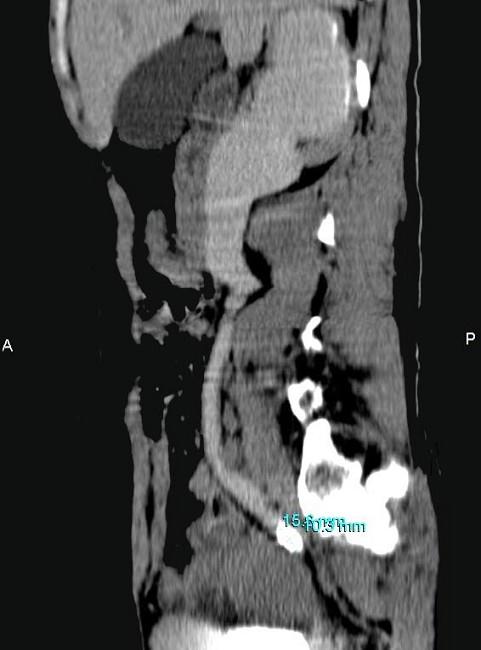

问题 女,42岁,反复右下腹部绞痛向会阴部放射1 月,CT检查如图示,下列诊断正确的是 ( )

选项 A、右侧输尿管下段结核,其上方输尿管扩张积水 B、右侧输尿管下段炎性狭窄,其上方输尿管扩张积水 C、右侧输尿管中段结石,其上方输尿管扩张积水 D、右侧输尿管下段结石,其上方输尿管扩张积水 E、右侧输尿管上段结石,其上方输尿管扩张积水

答案 C